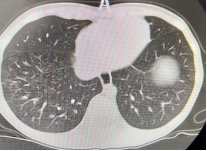

以下为呼吸专业典型病例分享:

图片5:气管内膜结核及重症支原体肺炎所致气道阻塞、塑性支气管束